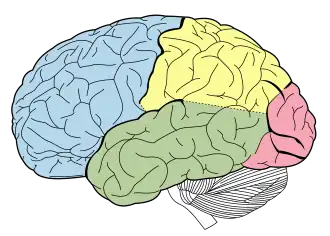

De hersenkwabben van de grote hersenen ■ frontale kwab - voor ■ occipitale kwab - achter ■ temporale kwab - zijkant Mensen hebben van deze vier kwabben er ieder twee, links en rechts in het hoofd. De kleine hersenen zijn in zwart-wit onder de grote hersenen te zien. | ||||